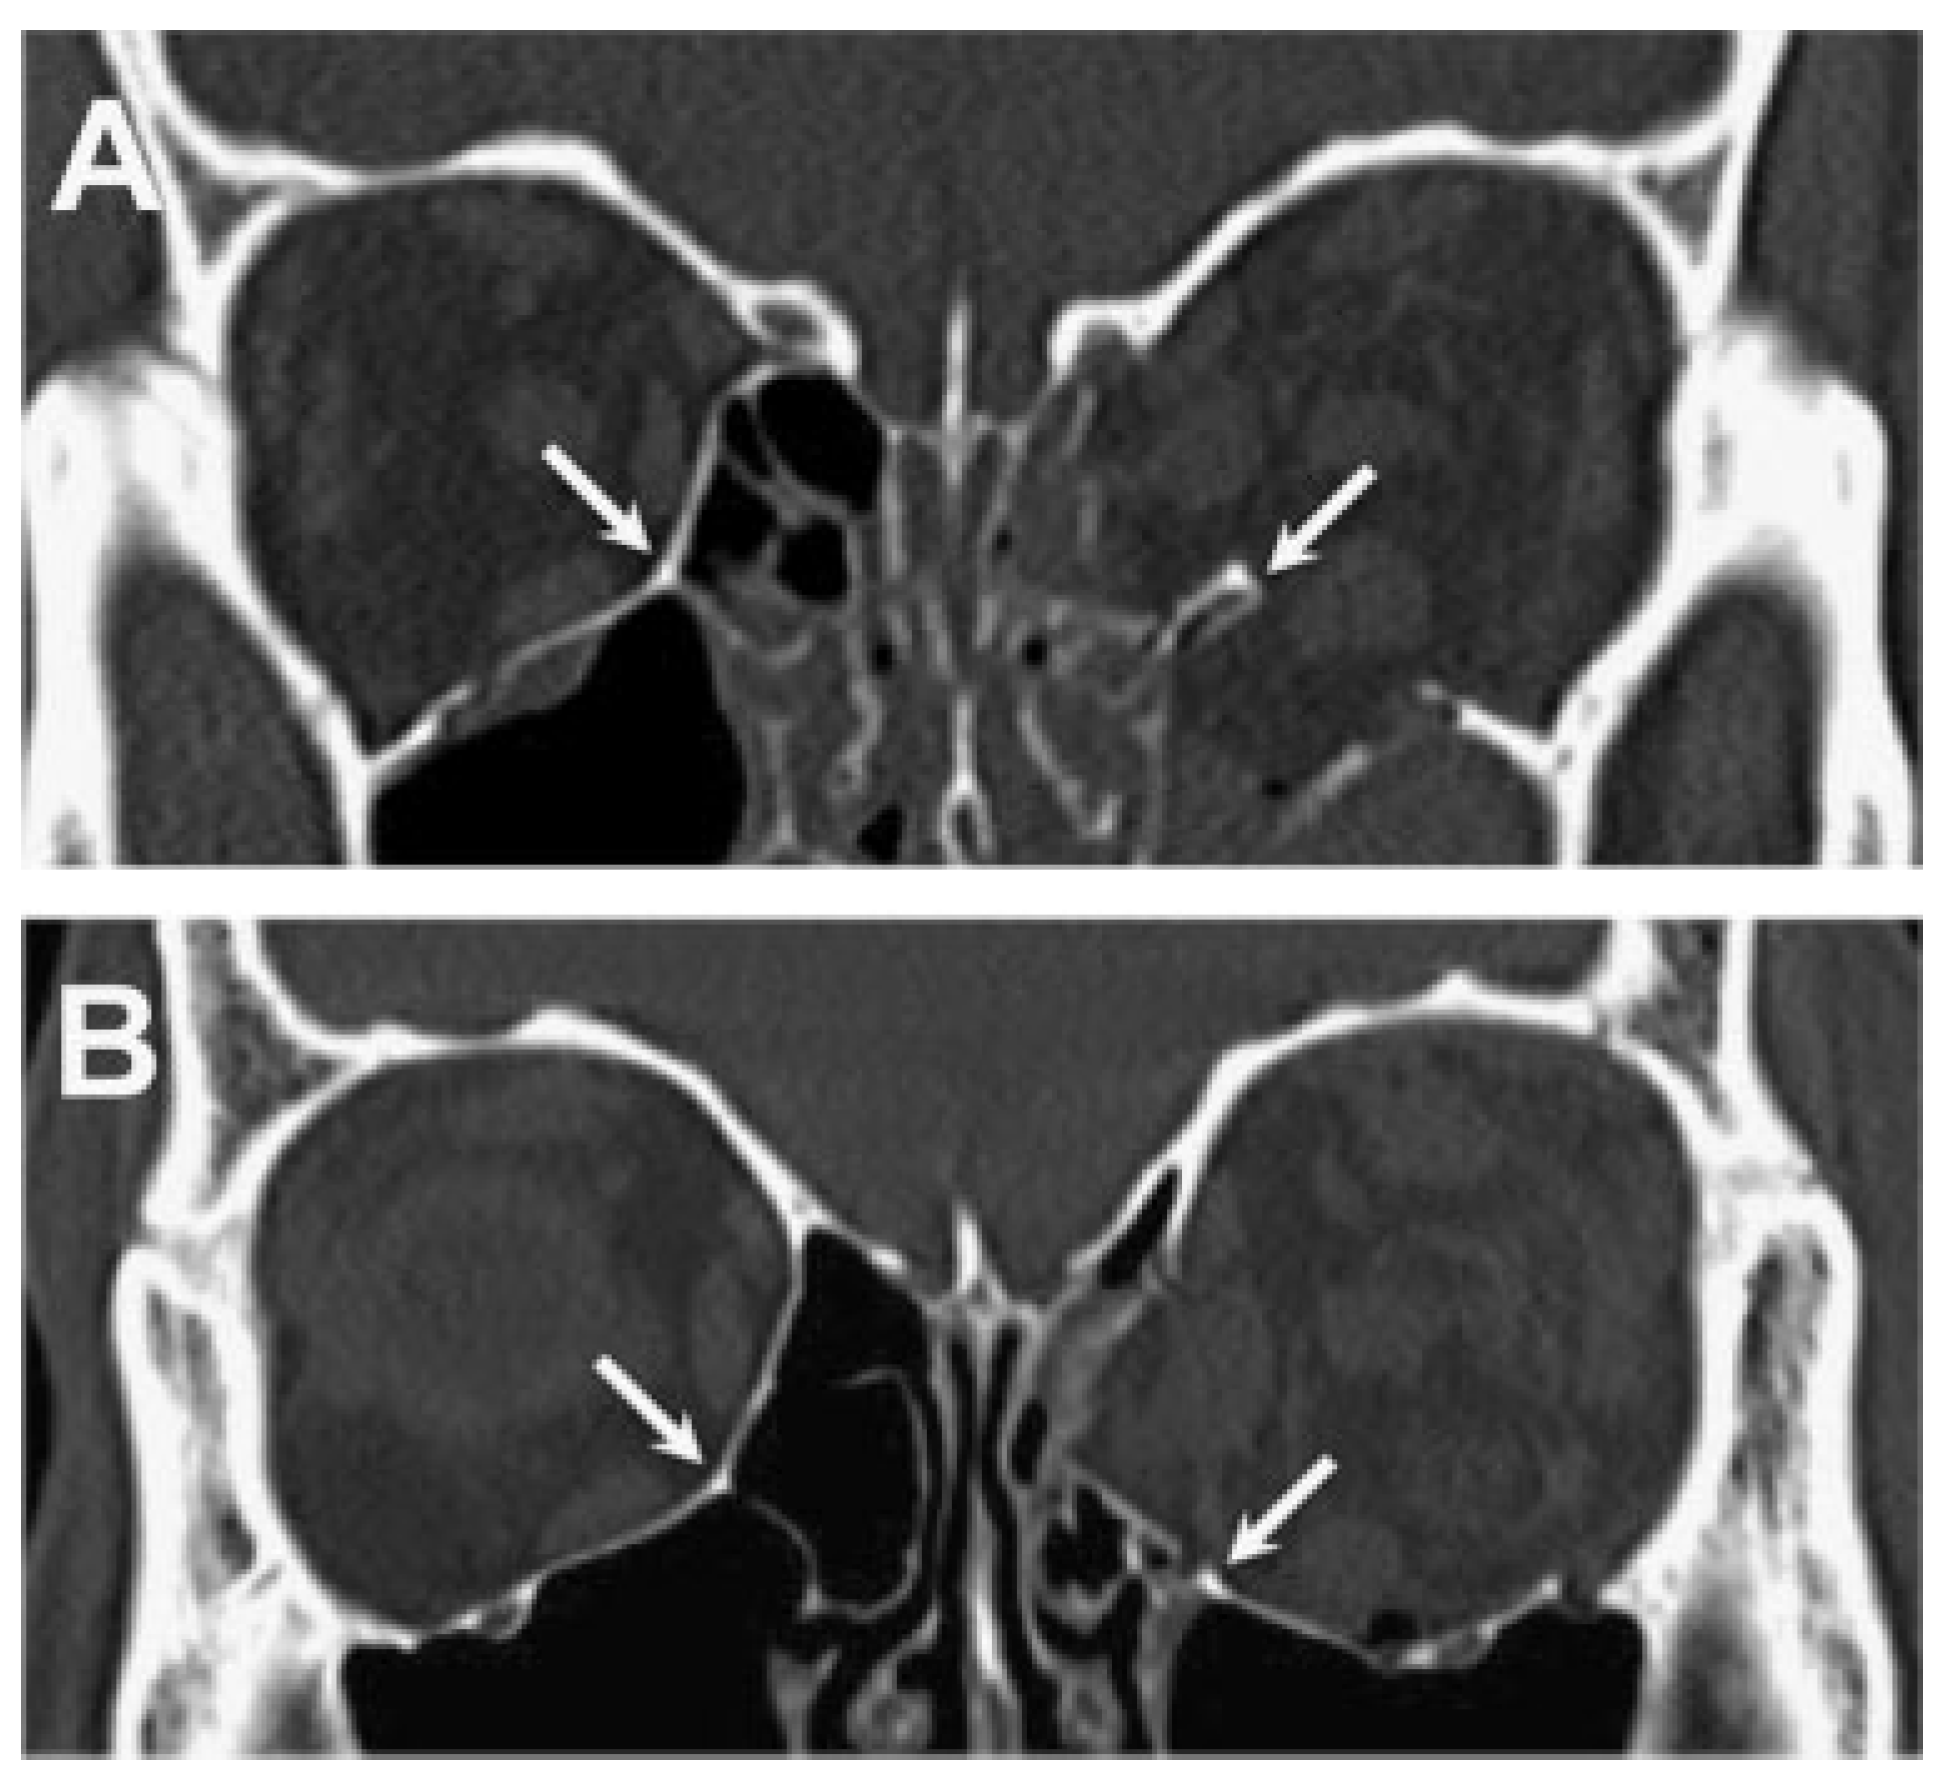

The most commonly fractured walls of the orbit are the floor and medial wall, and repair is indicated in cases of extraocular muscle entrapment, diplopia, globe malposition, and signifi-cant orbital volume expansion [1,2,3,4,5] . Combined fractures of the floor and medial wall are more likely than isolated orbital wall fractures to require treatment due to increased volume expansion; they are often associated with compromise of the inferomedial strut at the ethmoid-maxillary junction (Figure). The large size of these fractures and the loss of internal bony support can make surgical repair particularly challenging. Several techniques have been described to deal with this fracture pattern using a variety of implant materials and surgical approaches [6,7,8,9,10] . However, the goal of restoring the normal contours of the bony orbit while avoiding post-operative complications remains difficult to achieve. We herein describe a repair technique and report a case series using preshaped porous polyethylene (PPE)/titanium im-plants through a combined transconjunctival and transcar-uncular approach with disinsertion of the inferior oblique muscle.

Figure 1. The inferomedial strut (arrows), shown in coronal computed tomography scan images of two different patients with combined orbital floor/medial wall fractures. Intact left strut (A), and fractured/ displaced strut (B).